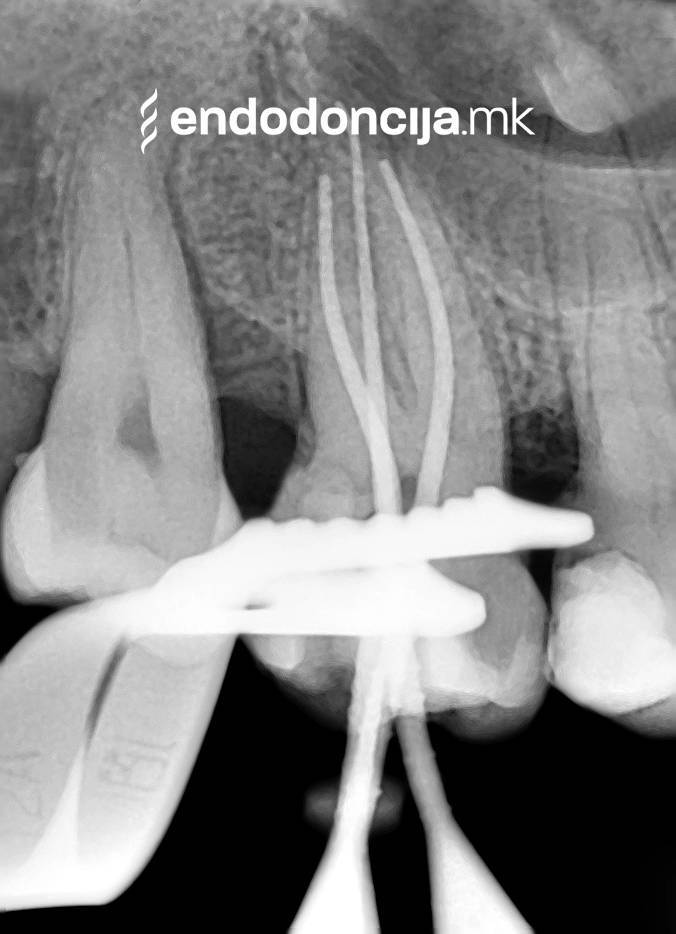

Κατά τη διάρκεια της επεξεργασίας του ριζικού σωλήνα, τα λεπτά όργανα ενδέχεται να σπάσουν. Αυτό μπορεί να αποτελέσει εμπόδιο για την πλήρη προετοιμασία και τον καθαρισμό του ριζικού σωλήνα. Με μια μικροσκοπική επεξεργασία του ριζικού σωλήνα μπορεί να είναι δυνατή η απομάκρυνσή τους υπό ορισμένες συνθήκες, χωρίς να καταστρέφεται η ουσία των δοντιών.

Κατά τη διάρκεια προηγούμενων θεραπειών, το δόντι μπορεί όχι μόνο να έχει αποδυναμωθεί από τη μηχανική επεξεργασία του ριζικού σωλήνα αλλά και από τη στερέωση και την αγκύρωση ενός ρίζα. Όταν αναθεωρείται η επεξεργασία ενός ριζικού καναλιού, αυτοί οι πείροι πρέπει να αφαιρούνται όσο το δυνατόν πιο προσεκτικά για να διατηρούν σημαντική ουσία των δοντιών.

Οι υπηρεσίες του Ειδικού Τμήματος Ενδοδοντικής δεν περιορίζονται καθόλου στη συμβατική επεξεργασία ριζικών καναλιών. Αντιμετωπίζουμε αποκλειστικά τους ασθενείς μας με τα νεότερα υλικά και όργανα με μικροσκόπιο, προκειμένου να είμαστε σε θέση να καθαρίσουμε εντελώς και να προετοιμάσουμε όλα τα κανάλια πριν τα γεμίσουμε.